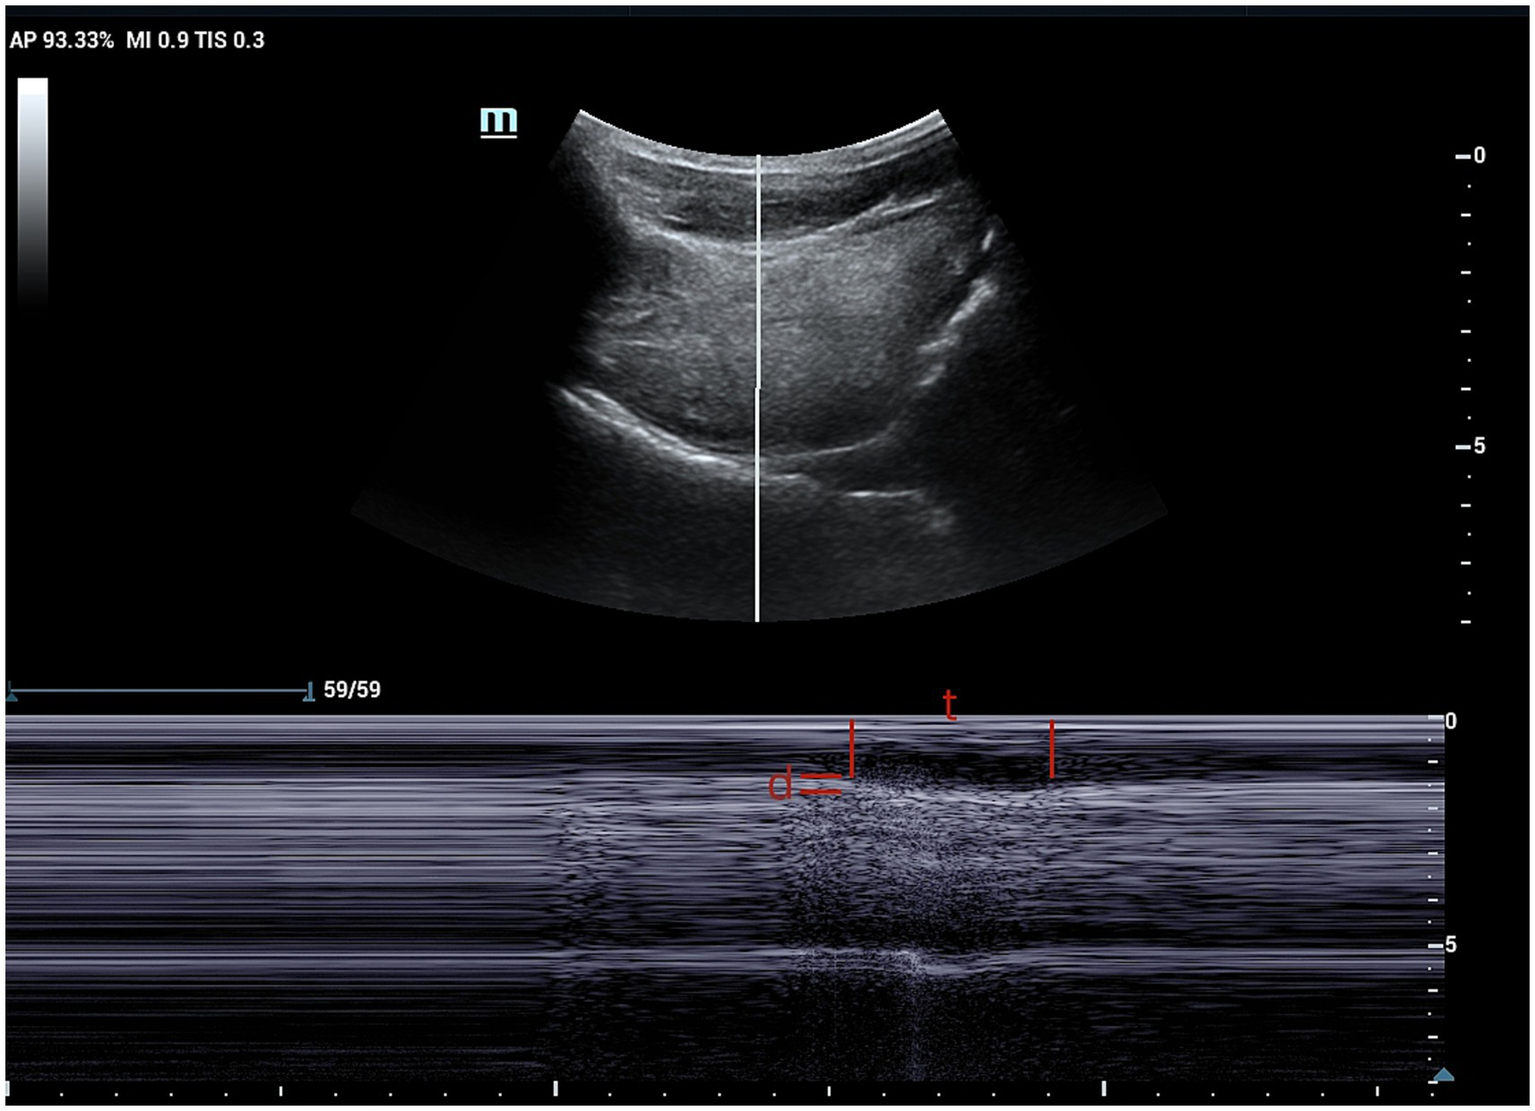

Figure 2

M-mode ultrasound image showing time and distance of genioglossus movement. The sampling line is placed at 2 cm from the hyoid bone. t, time of genioglossus movement; d, distance of genioglossus movement.